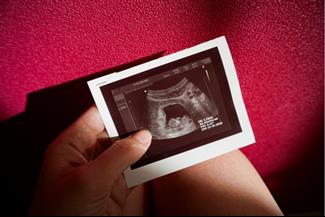

מאת: מערכת אינפומד 19/02/2019אם עדיין לא עשית אולטרסאונד, השבוע תפגשי לראשונה את העובר שלך. מה תוכלי לראות באולטרסאונד ומה את צפויה להרגיש בשבוע... לכתבה המלאה